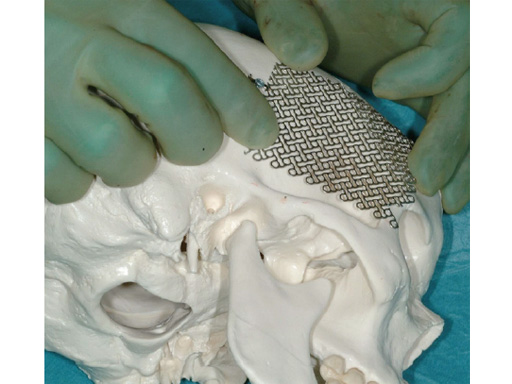

Case 1: Camouflaging of deficient zygomatic prominences by mesh augmentation. a 19-year-old man with a typical-angle class iii appearance is shown preoperatively (fig 4a) and postoperatively (fig 4b). after preoperative planning, a bimaxillary osteotomy with advancement of the upper jaw and backwards movement of the lower jaw following bisagittal split osteotomy was performed. alternative options to augment the malar bone are surgical osteotomy of the malar bone with outwards movement of the zygomatic prominences, high le fort i osteotomy with onepiece movement of the maxilla together with the zygomatic prominence, using other biomaterials than meshes to augment these prominences. in this case, the average prominence in an adult caucasian patient was mimicked by contouring a 0.6 mm thick, 3-D mesh using the artificial skull.